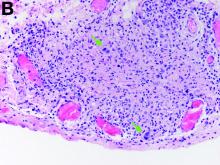

The gallbladder (Figure B) as well as the intraoperative liver biopsy (Figure C; insert showing cells under higher power) showed non-necrotizing granulomas along with scattered infiltration by atypical large cells morphologically consistent with Hodgkin-Reed-Sternberg cells in a lymphoid background (Figures B, C, green arrows). Immunohistochemistry showed these were positive for CD30 (Figure D, liver biopsy), weakly positive for PAX5, and negative for CD15, CD20, CD79a, and ALK-1. Given the pathologic findings, the patient was diagnosed with Hodgkins lymphoma.

The patient had a history of mediastinoscopy and lymph node biopsy in the past at an outside hospital with reported noncaseating granulomas and no other abnormalities; those slides could not be obtained for independent review. Primary lymphomas of the liver are exceedingly rare, but advanced lymphoma can have liver involvement.1 Hodgkins lymphoma of the liver is extremely uncommon.2 It can present with fever, hepatomegaly, and jaundice.1 The diagnostic yield of a liver biopsy ranges from 5% to 10% depending on core versus wedge biopsy.1 Pathologically, there is portal inflammation and atypical histiocytic aggregates but Hodgkin-Reed-Sternberg cells are required for diagnosis. These cells stain positive for CD15 and CD30 in around 80% of cases.3 Lymphoma should remain in the differential when granulomas are seen in the liver biopsy. Our patient clinically decompensated by the time the diagnosis was confirmed. The family decided not to pursue aggressive treatment in hospital and the patient was discharged home where she expired.